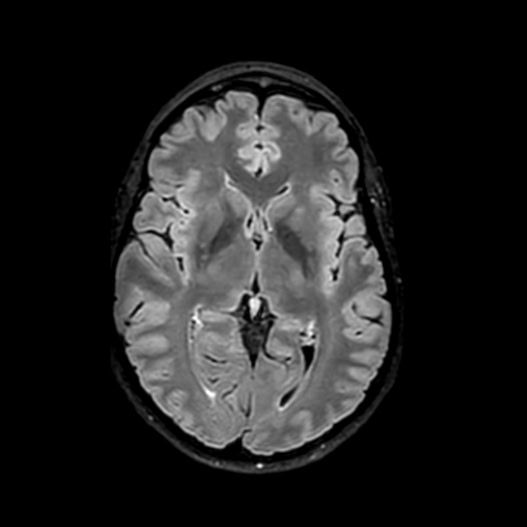

Conditions Detectable with Our Whole Body MRI

Whole Body Scan